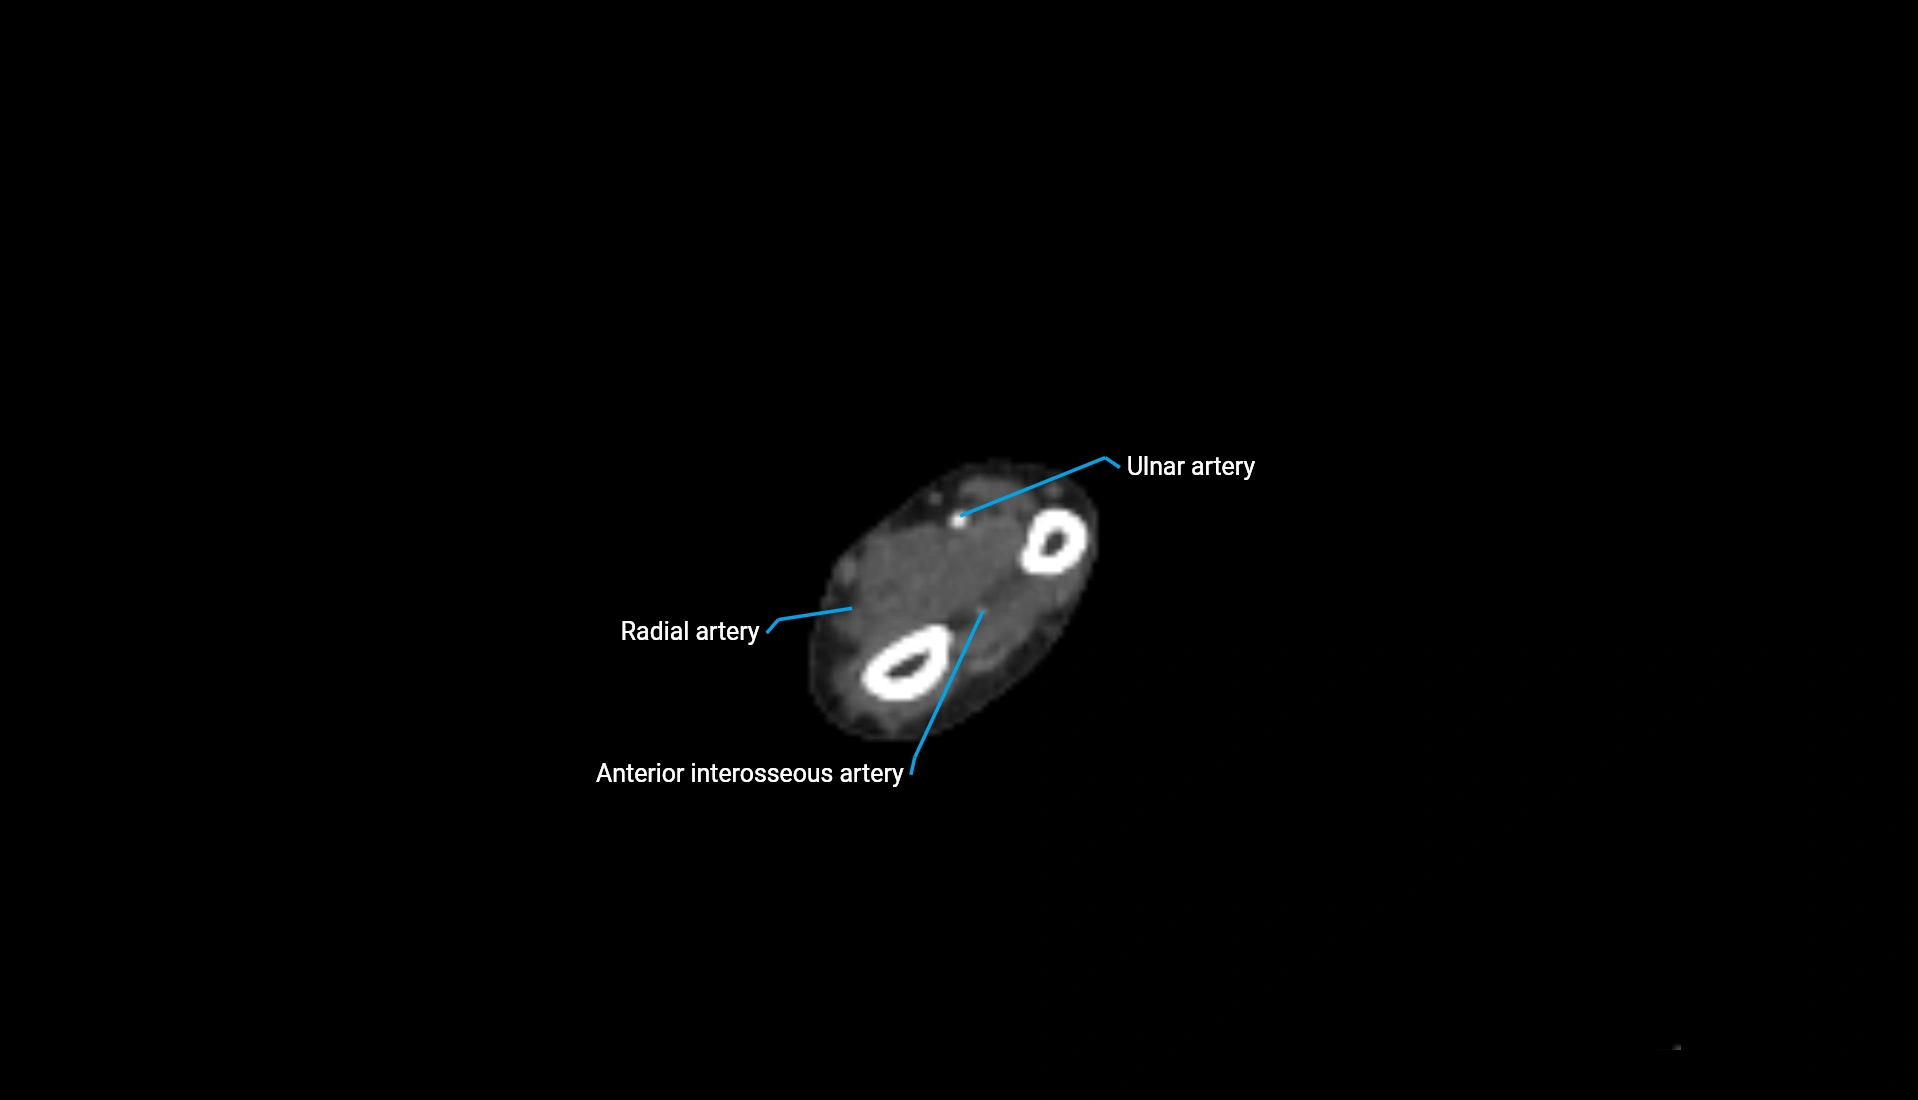

CT Appearance

Non-Contrast CT:

• Cortex: High-density, sharply defined

• Subchondral bone: Dense cancellous matrix

• Articular surface: Smooth concave contour articulating with the capitellum

• Excellent for evaluating bone integrity, alignment, and subtle fractures